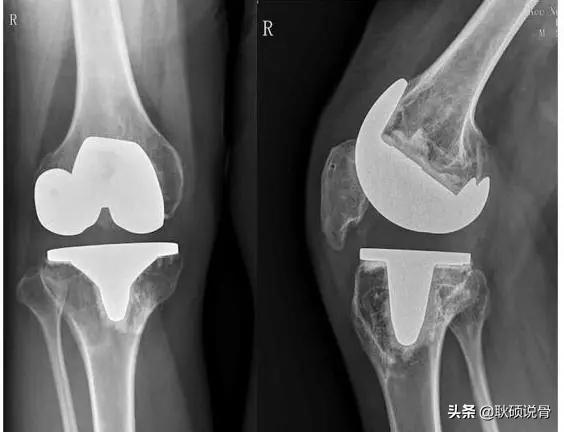

第四种,全膝关节置换术(TKA),对于严重膝关节骨刺,严重影响生活的,这种方式缓解疼痛的效果显著,可以一次性解决已经发生畸形的膝关节,随着膝关节生存率越来越高,术后在疼痛、关节功能及活动度等方面均有明显的改善,极大地提高病人的生活质量,以及TKA手术技术的日渐成熟,如今已经成为国际国内治疗膝关节骨性关节炎最流行的骨科手术。